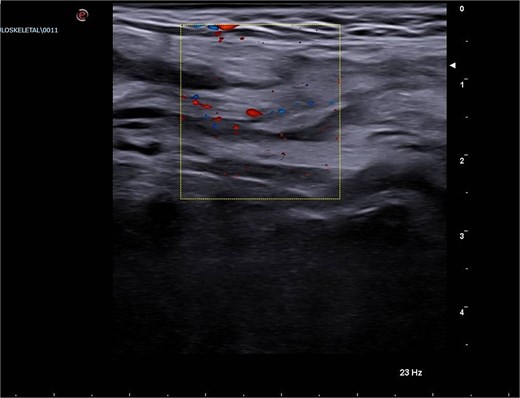

A scrotal ultrasound revealed a grossly hyperechoic area within the right inguinal canal measuring 50 × 20 mm associated with fine vascular spots on Doppler imaging, initially interpreted as thickened omental adipose tissue. No significant changes were observed during Valsalva maneuver, raising suspicion for an incarcerated omental hernia (Figs 1 and 2).

Emergency Department ultrasound images showing a hyperechoic mass occupying the right inguinal canal.

Emergency Department ultrasound images showing a hyperechoic mass occupying the right inguinal canal, with fine vascular signals on color Doppler. The lesion exhibited no change during the Valsalva maneuver and was initially suspected to be an incarcerated omental hernia.